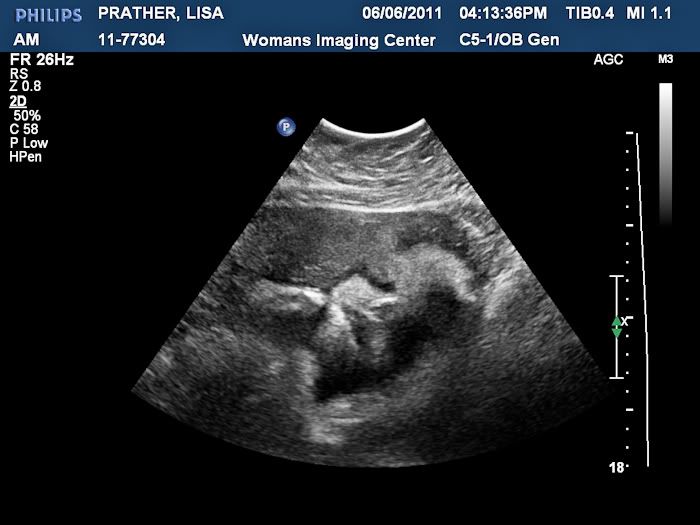

We had an ultrasound today and got to see our baby boy! It was so wonderful to see him, but even better to find out that he is still perfect. He weighs 4 pounds and 11 ounces right now!

Still a boy!